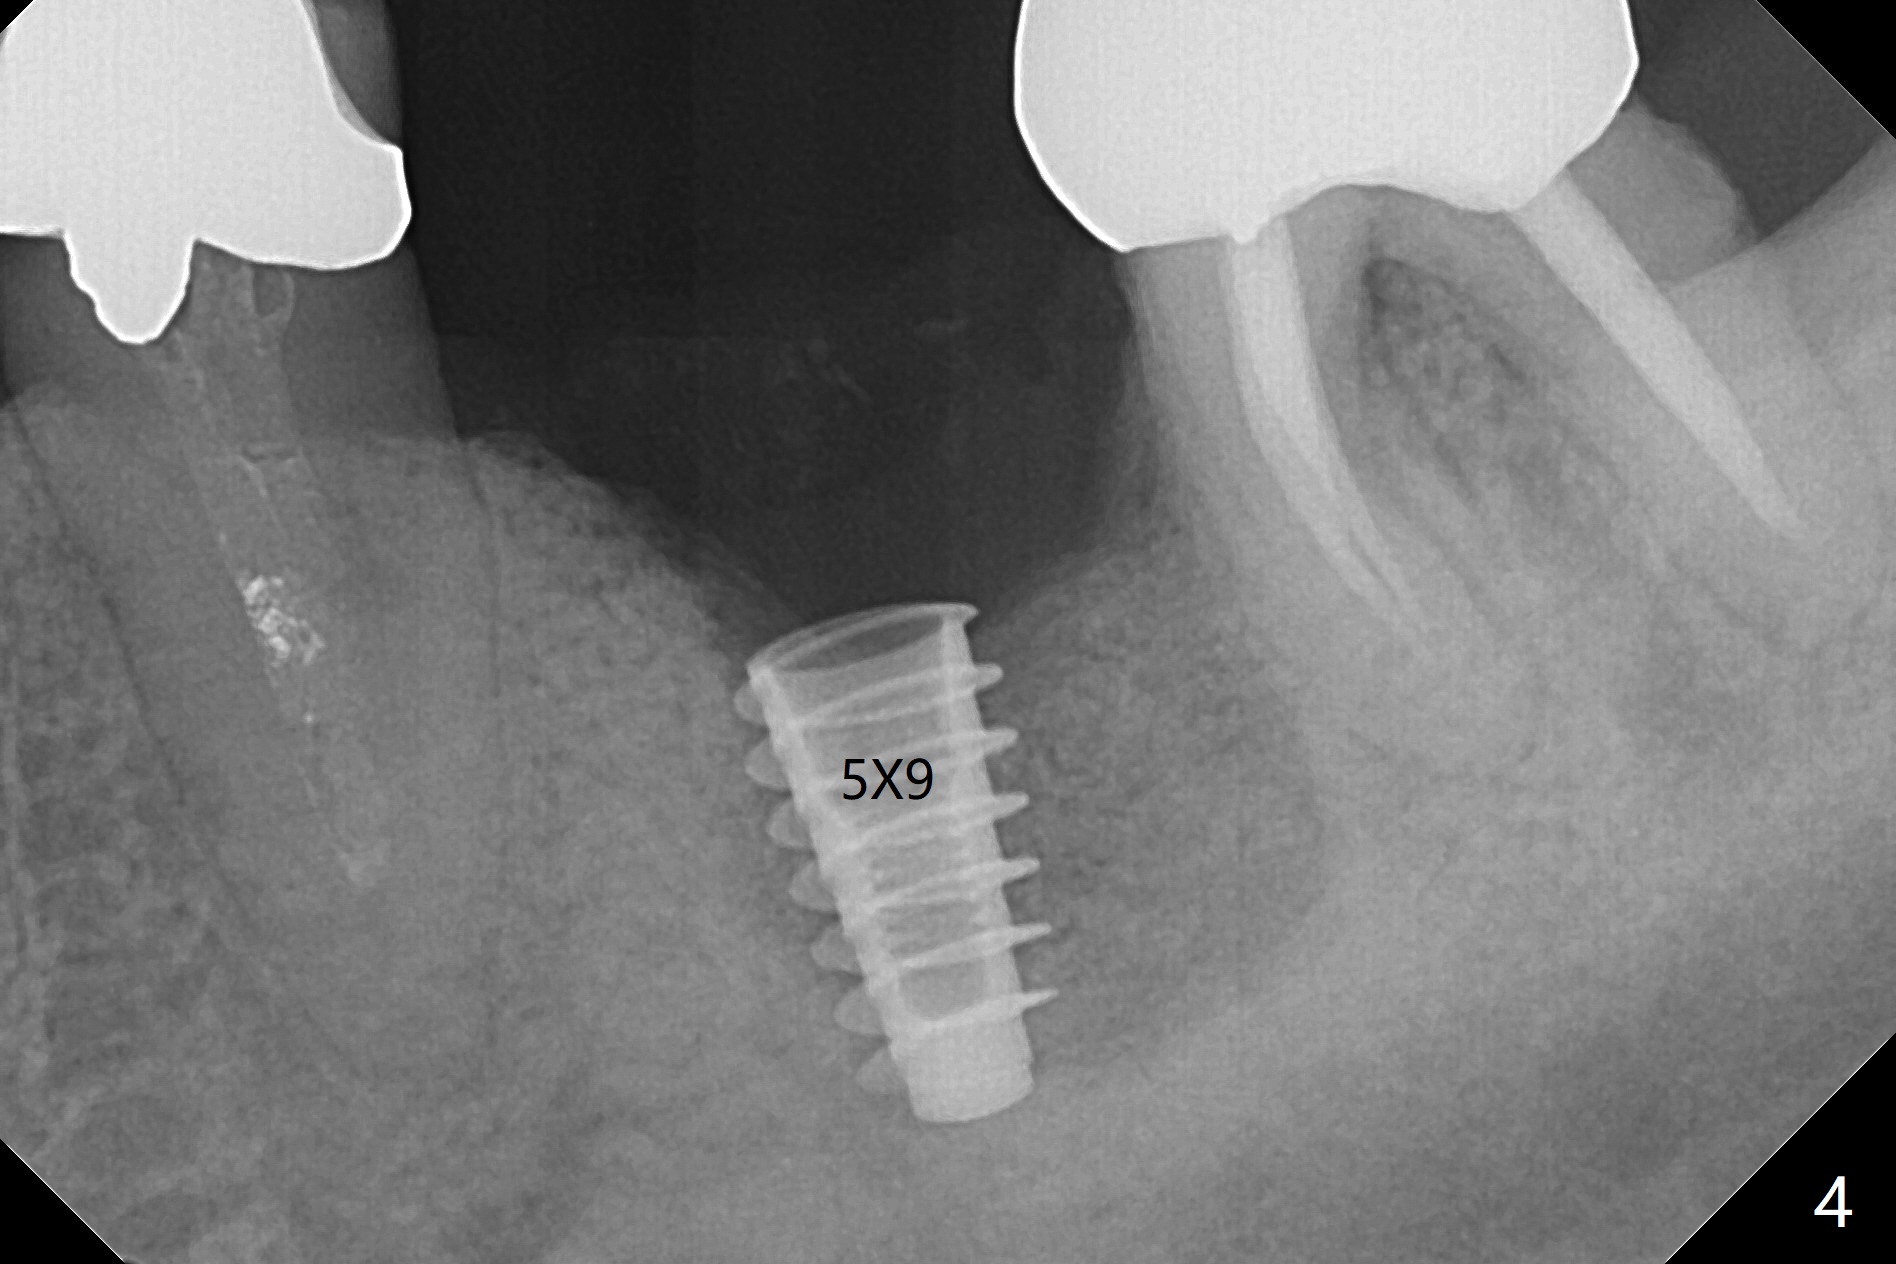

When the patient returns 4 months post implant removal and bone graft, the ridge at #19 is concave with a small hole which communicates with the underlying bone (Fig.1 <). The low density bone in the middle of the socket is ignored (Fig.2 *, 3 S (soft)). With under drilling, primary stability of tissue-level taps is lower. A bone-level dummy implant is placed with low torque (Fig.4). After removal of granulation tissue distal to the osteotomy, a larger implant is inserted with ~15 Ncm; mixture of autogenous bone and allograft is packed (Fig.5 *). The latter is covered by 12x12 mm BioXclude and sutured with 4/0 Chromic Gut tension free. 植牙后6.5月牙槽嵴饱满,角化龈宽(图六(刚开始浸润麻醉))。术后6.5月切开证实植体上面没有骨质覆盖(如图七:*),第一螺纹可能暴露(>)。由于骨质吸收,大号基台置入没阻挡,或者困难(图八),第一螺纹暴露(>)需要再次植骨(图九:*)。放置大号基台(6x6(4)毫米)和植骨使萎缩牙槽嵴部分得到修复(图十,与Uncover前(图六)对比)。Uncover时即刻置入修复性基台好处是利用基台牙龈外部分强化牙周敷料固定,基台中央放置一个棉球后,敷料可以插入基台中央进一步增加固位(图十一(舌侧观):*)。